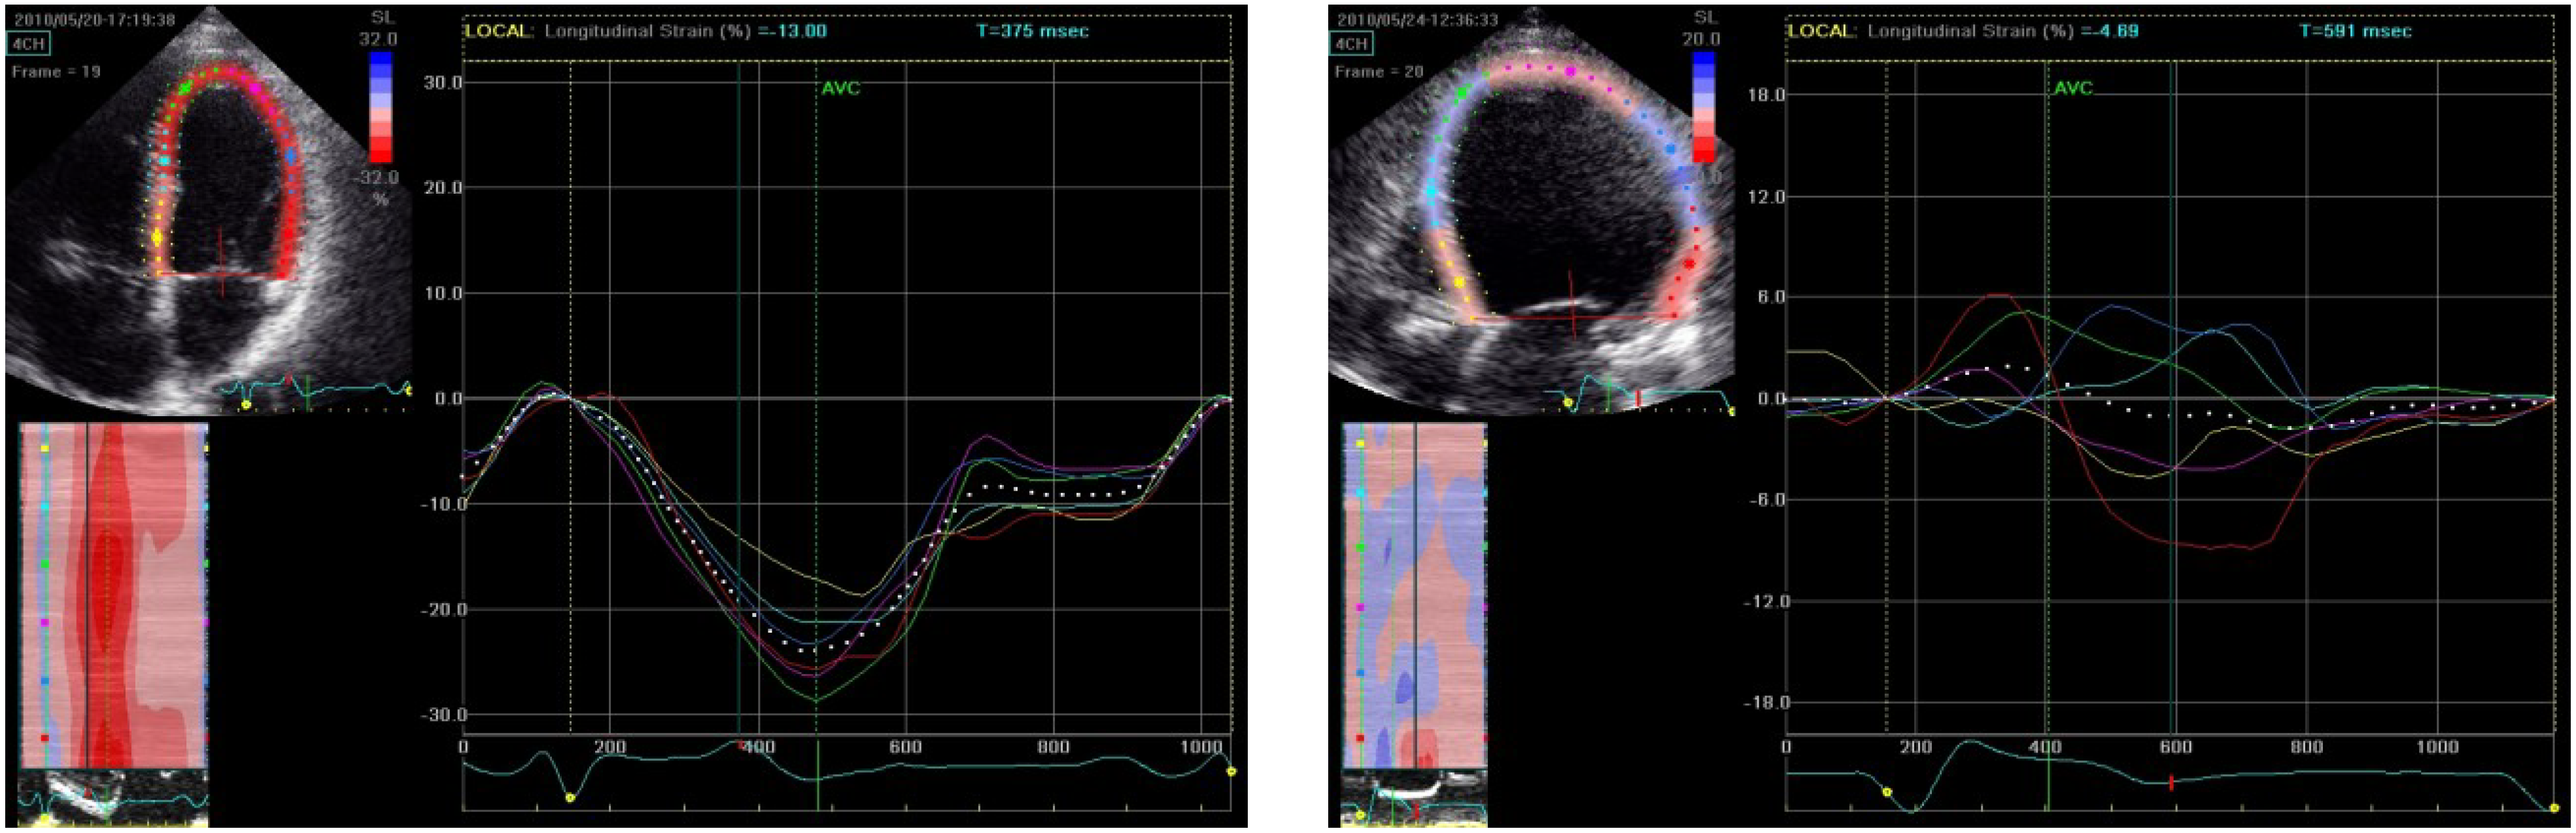

Case 2: Chemotherapy Associated Cardiotoxicity